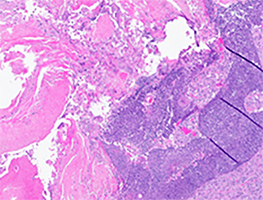

Subsequently she underwent left cheek wide local excision with left superficial parotidectomy, left neck dissection and left cervicofacial rotational flap. Gross examination revealed a discoid skin excision measuring 3.2 x 3.4 cm in surface with an excisional depth of 1.4 cm. Cut sections revealed a 1.6 x 1.6 x 0.7 cm centrally located tan, granular, semi-firm nodule abutting the deep margin (Fig. 4). Microscopic examination demonstrated a well circumscribed intradermal/ subcutaneous nodule with a thin fibrous capsule composed of peripherally located basaloid cells surrounding central collections of eosinophilic and shadow cells with numerous foreign body type giant cells consistent with pilomatricoma (Fig. 5A-5B)

Fig 5A. x4

Fig 5B. x20